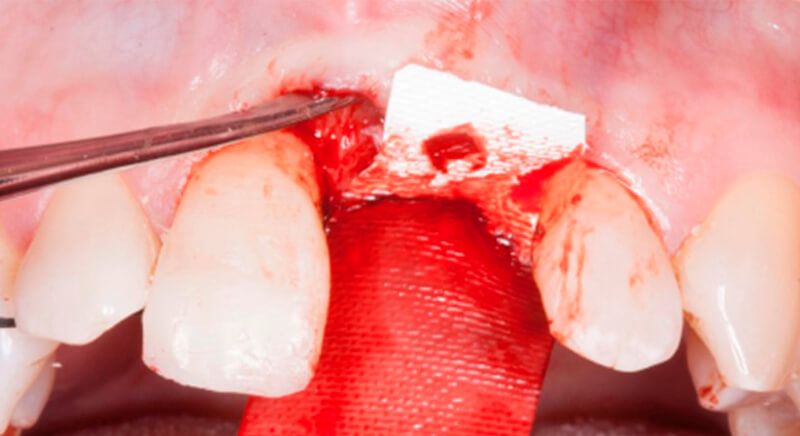

The socket was filled with a xenograft after the extraction and a graft of connective tissue was placed in the vestibular area of the two upper central incisors.

The tissue with epithelium was taken from the palate and de-epithelialized outside of the mouth. This obtains a lamina propria graft with better density and quality than if it were obtained with a single incision to the palate.